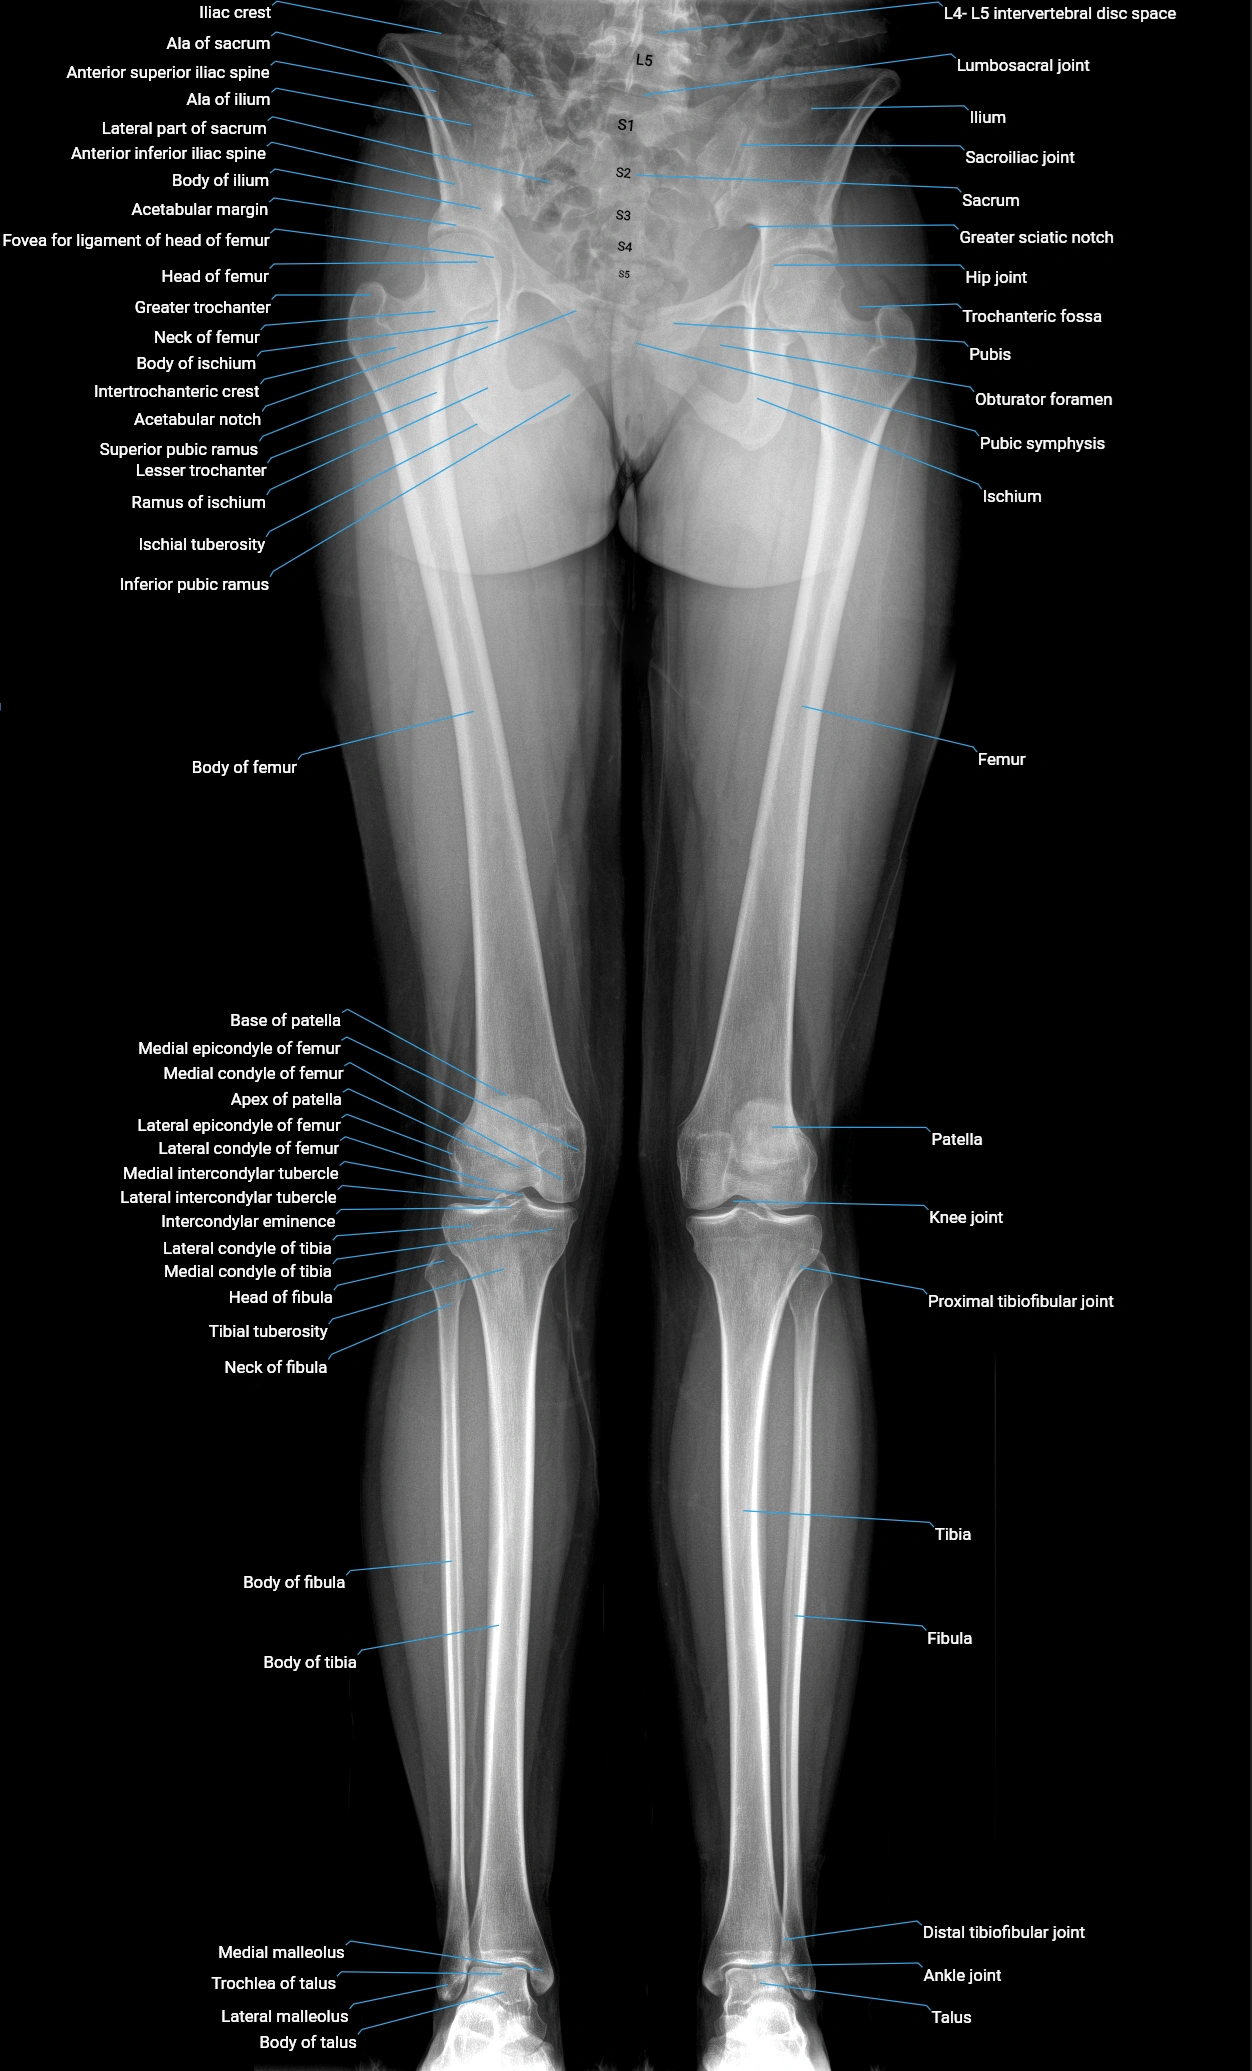

Acetabular margin (Acetabular rim)

The acetabular margin, also called the acetabular rim, is the bony edge of the acetabulum, the cup-shaped cavity on the lateral aspect of the pelvis that articulates with the head of the femur to form the hip joint. The acetabular margin consists of the superior, anterior, and posterior borders of the acetabulum and is interrupted inferiorly by the acetabular notch.

The rim provides attachment for the acetabular labrum, a fibrocartilaginous structure that deepens the acetabulum, increasing hip joint stability. The transverse acetabular ligament bridges the acetabular notch, completing the bony ring. Superiorly, the margin bears the greatest load during standing and gait, making it the most common site of degenerative changes.

The acetabular margin is clinically significant in femoroacetabular impingement (FAI), acetabular fractures, hip dysplasia, and osteoarthritis. Its morphology (depth, coverage, and orientation) is a key factor in hip biomechanics and surgical planning, especially in arthroscopy and hip preservation surgery.